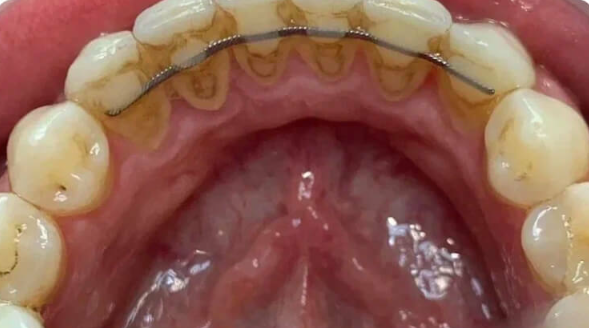

Профессиональная гигиена особенно важна при ортодонтическом лечении, ведь в повседневной жизни, дома, очень сложно поддерживать должный уровень гигиены полости рта! Даже если вы используете ирригатор и специальные ёршики! В нашей рубрике «до/после» вы видите то, что может быть с зубами при лечении брекетами, если не проводить своевременную чистку у врача-стоматолога. Марухно Дарья Александровна провела профессиональную чистку в несколько этапов, чтобы вернуть пациентке белизну ее собственных зубов! Брекет-система была поставлена не в нашей клинике, и почему пациентка не обратилась за профессиональной помощью раньше-вопрос) Но в данном случае, главное – итог! Кровоточивость после даже обычной чистки в такой клинической ситуации – естественный результат. Ведь обильный зубной налёт и зубной камень вызывают воспаление дёсен в виде гингивита, а порой даже пародонтита.

Доктор: Марухно Дарья Александровна